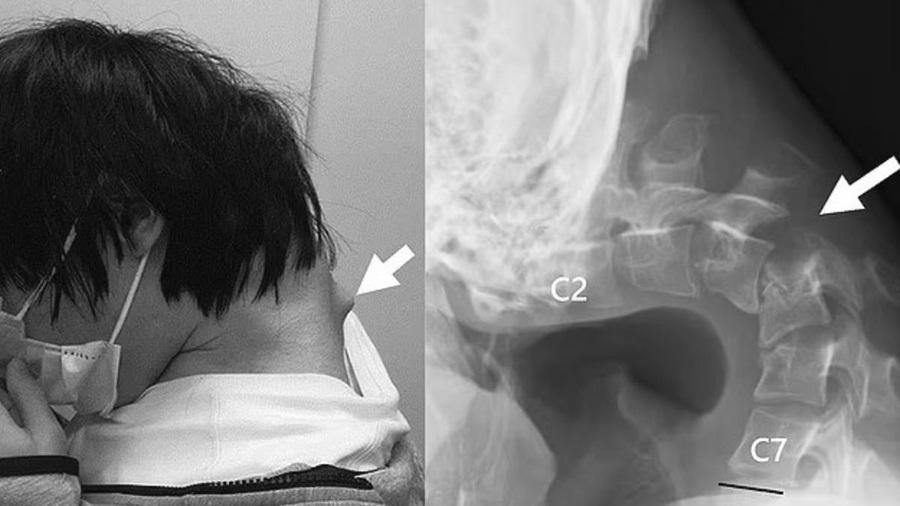

英國《每日郵報》稱,這宗恐怖「垂頭症」(dropped head syndrome)病例於2023年在整形外科期刊JOS Case Reports刊登,X光片可見患者的頸椎明顯90度彎曲,那名男患者頭向前垂,後頸有一角型物體凸出。報道指,患者幼時活潑開朗,但青少年時期遭欺凌變成宅男,退學後躲在房裡數年。他在房間裡只低頭玩手機遊戲,結果導致嚴重垂頭症。除了外觀問題,該男子嚴重頸痛長達半年,也開始抬不起頭,加上吞嚥困難、體重暴降,最終尋求治療。

醫生初時嘗試用頸圈矯正該患者的頸椎,但因他戴上頸圈後感到麻痺,最後要做手術。醫生首先切除其小部分頸椎骨,以及頸部長出的疤痕組織,然後再安裝上螺絲和金屬桿承托其頭部並矯正彎曲的頸項。據悉,那名男子在手術後6個月,脊椎回復正常位置,他可容易抬頭至水平位置;後續1年跟進,他的抬頭和吞嚥問題也無再現。